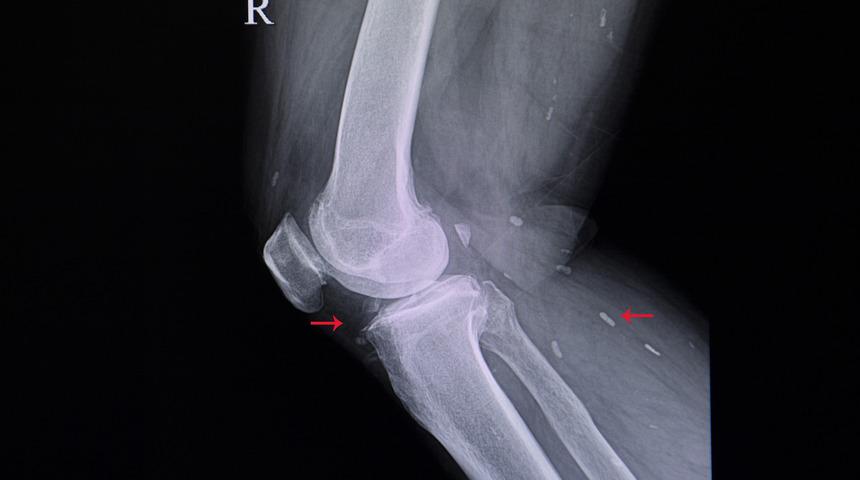

Kıkırdağın aşınmasıyla eklem ile kemik arasındaki mesafe giderek azalır ve sürtünmenin etkisiyle kemik başlarında ve eklemde deformasyon başlar. Bazen bu sürtünmenin etkisiyle bazen de çarpmaların etkisiyle, kıkırdak ya da kemiklerden küçük parçacıkların kopabilir. Eklem sıvısı içinde serbestçe dolaşan bu parçacıklar (eklem faresi) eklem yüzeyi ile temas ettiğinde ağrı, şişlik, kızarıklık gibi şikayetlere sebep olur.

3. Evre: Kıkırdak kaybı artmış, eklem arası boşluk %50’nin üzerinde daralmıştır. Buna bağlı olarak bacaklar dışa doğru (parantez bacak) eğilmeye başlar. Ağrı dinlenmeyle geçmez hale gelir. Diz çökmek ve yeniden doğrulmak neredeyse imkansız hale gelmiştir.

4. Evre: Eklem üzerinde kıkırdağın tamamen kaybolduğu alanlar görülür. Ağrı sadece hareketle değil dokunmayla bile başlayabilir. Hasta sık sık uykusundan ağrıyla uyanır ve dizine yorganın değmesine bile tahammül edemez. Eklem aralığı neredeyse kalmamıştır. Tahribat sadece eklemde değil kemiklerde de rahatlıkla görülür.

Cerrahi yöntemler kireçlenme tedavisinde en son seçenek olarak değerlendirilir. Hastanın durumuna ve kireçlenmenin evresine göre açık ya da kapalı (atroskopi) ameliyat yöntemlerinden uygun olanı seçilir. Eklem faresi ya da kas yırtılması atroskopik yöntemle tedavi edilebilir. Fakat 4. evre kireçlenme vakalarında büyük miktarda kıkırdak kaybı olduğundan, açık ameliyat tercih edilir.